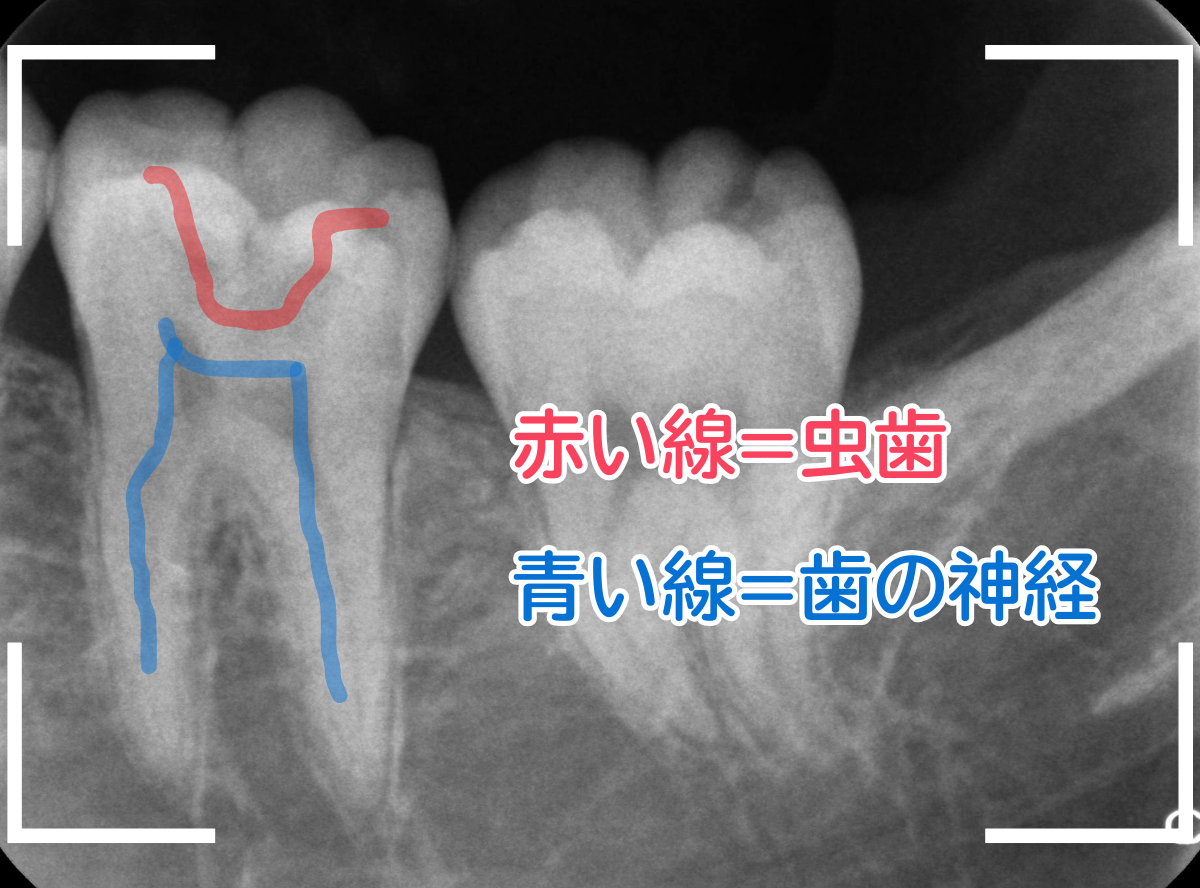

レントゲン写真で確認します。

青い線が神経、赤い線が虫歯の部分です。

やはり、小窩裂溝の中で大きな虫歯になっています。

レントゲンから想像した通り、手前の歯まで達した、かなり大きな虫歯です。

奥歯は、レントゲン所見とおり、かなり深い虫歯でした。